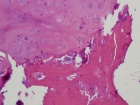

26 year old female with ten year history of right knee pain with intermittent swelling